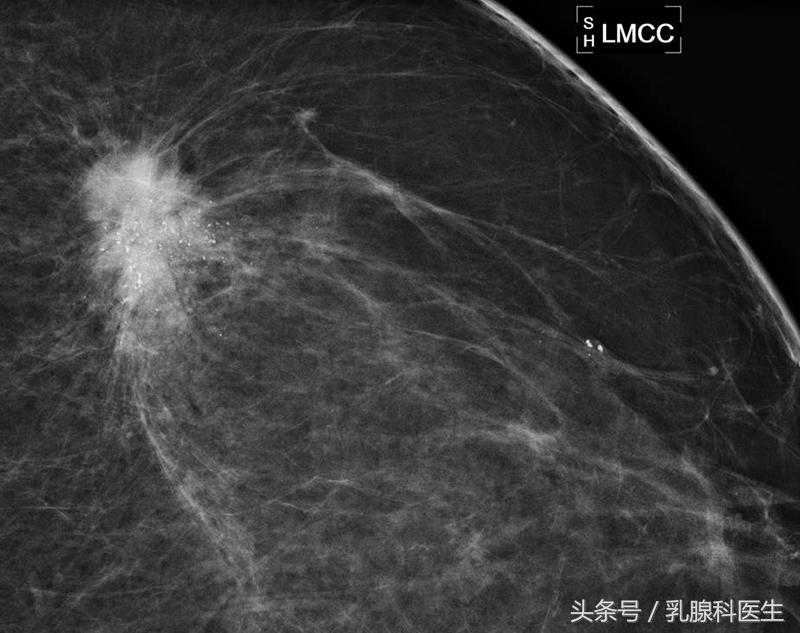

目前认为,适当的腹部隔离防护下,乳腺钼靶是被允许!乳腺钼靶的辐射剂量远远低于研究表明的可能会增加胎儿先天畸形和发育迟缓的的辐射剂量!乳腺核磁共振用于妊娠期和哺乳期女性乳腺诊断的前瞻性研究!也没有钆应用与妊娠期的安全性数据!